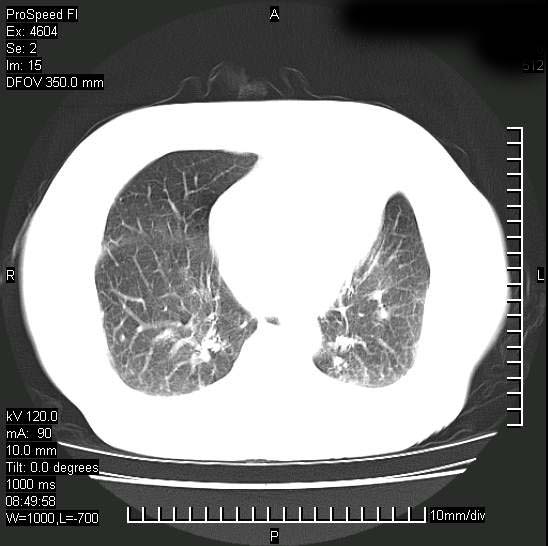

标题: CT15528:女性,79岁,近几日晚上高热,39度,仍咳少量血 [打印本页]

标题: CT15528:女性,79岁,近几日晚上高热,39度,仍咳少量血

十几年前曾患肺结核,一周前突咳血约100ml,中性粒细胞稍高,诊断两上肺陈旧结核,下肺炎症,给予抗炎治疗,近几日晚上高热,39度,仍咳少量血,4天前ct及今天ct上传。

今天ct

短短几天内,病变范围明显增多扩大,以左侧明显,而且双侧出现胸水,还是考虑感染.

支持  结核ban感染,节段性肺不张,支气管内膜结核可能

短短几天内,病变范围明显增多扩大,以左侧明显,而且双侧出现胸水,我更多考虑左侧中心性肺癌并并阻塞性不张及肺炎,炎症变化也太快了!

继发性结核感染加重。左侧合并有支气管内膜结核。

无论是肿瘤还是炎症4天的时间都发展够快的,并且还在治疗中,如果说是左肺癌那么右肺的病变不好解释,本人更加倾向于炎症,左肺舌叶支气管被痰栓或血凝块堵塞,造成阻塞性肺炎。

1)两肺结核并感染。2)不排除左肺上叶中央型肺癌并阻塞性肺炎、肺不张可能;建议行纤支镜检查。3)右肺门及纵隔淋巴结肿大。4)双侧胸腔积液。

陈旧性肺结核及左下肺不张,咯血后肺部感染,双胸腔积液,高热可能与痰液引流不畅有关。